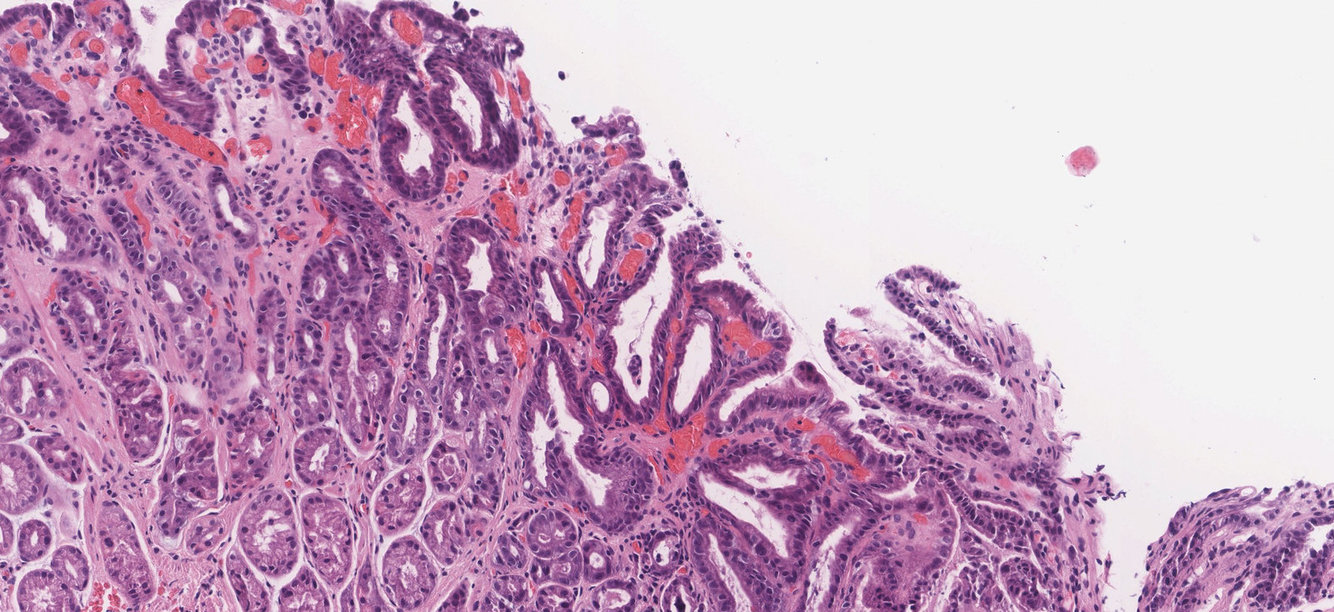

Gastric Adenocarcinoma

There are atypical cells forming glandular structures (green circles) of various sizes with intraluminal debris.

These findings are consistent with gastric adenocarcinoma.